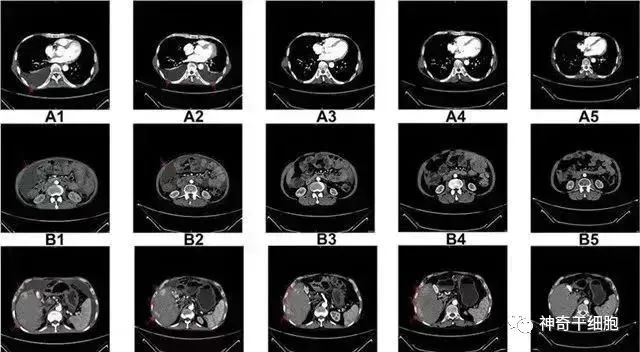

△ NK细胞治疗前和治疗期间的CT扫描结果

案例2:国内一名60岁的卵巢癌晚期患者,在接受了体外扩增,高度活化的同种异体NK细胞的治疗后,CA125水平从11,270降至580,所有腹水都消失了。此外,CT扫描的肿块体积减小,并且没有出现副作用。

案例3:一名广泛期小细胞肺癌患者,在进行4个疗程化疗和4次高度活化NK细胞回输后,患者第一次进行治疗后的CT复查,结果显示,肿瘤缩小到了原来的1/8。而且距发病第六年的CT复查中,仍旧没有发现任何异常及复发的迹象。